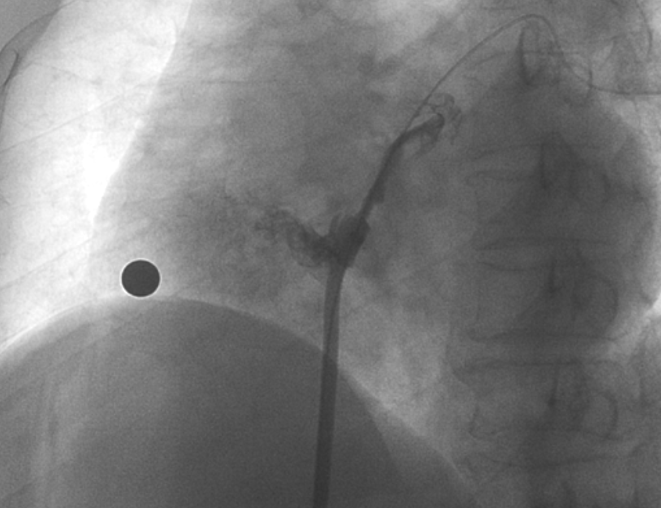

造影顯示長隧道型PFO

術(shù)中造影顯示患者為PFO且長隧道型,目前市場上已商業(yè)化的PFO封堵器難以滿足該患者解剖結(jié)構(gòu)封堵需求。迪創(chuàng)醫(yī)療自主研發(fā)的OmniSeal PFO封堵器自適應(yīng)性雙盤貼合設(shè)計能廣泛適應(yīng)不同PFO隧道長度的解剖結(jié)構(gòu)和形態(tài),其雙盤外包覆式阻流和隧道內(nèi)填充阻流相結(jié)合的雙重阻流設(shè)計,可為此患者實(shí)現(xiàn)有效封堵。與此同時,OmniSeal首創(chuàng)的完全可穿刺式設(shè)計,也為此患者最大程度地保留了房間隔區(qū)域穿刺通道,以實(shí)現(xiàn)全兼容未來可能的左心系統(tǒng)二次介入術(shù)。術(shù)終造影和心臟超聲顯示封堵完全、效果良好。作為OmniSeal的首例臨床應(yīng)用,本次手術(shù)的順利完成和優(yōu)異效果充分體現(xiàn)了產(chǎn)品的設(shè)計創(chuàng)新優(yōu)勢。